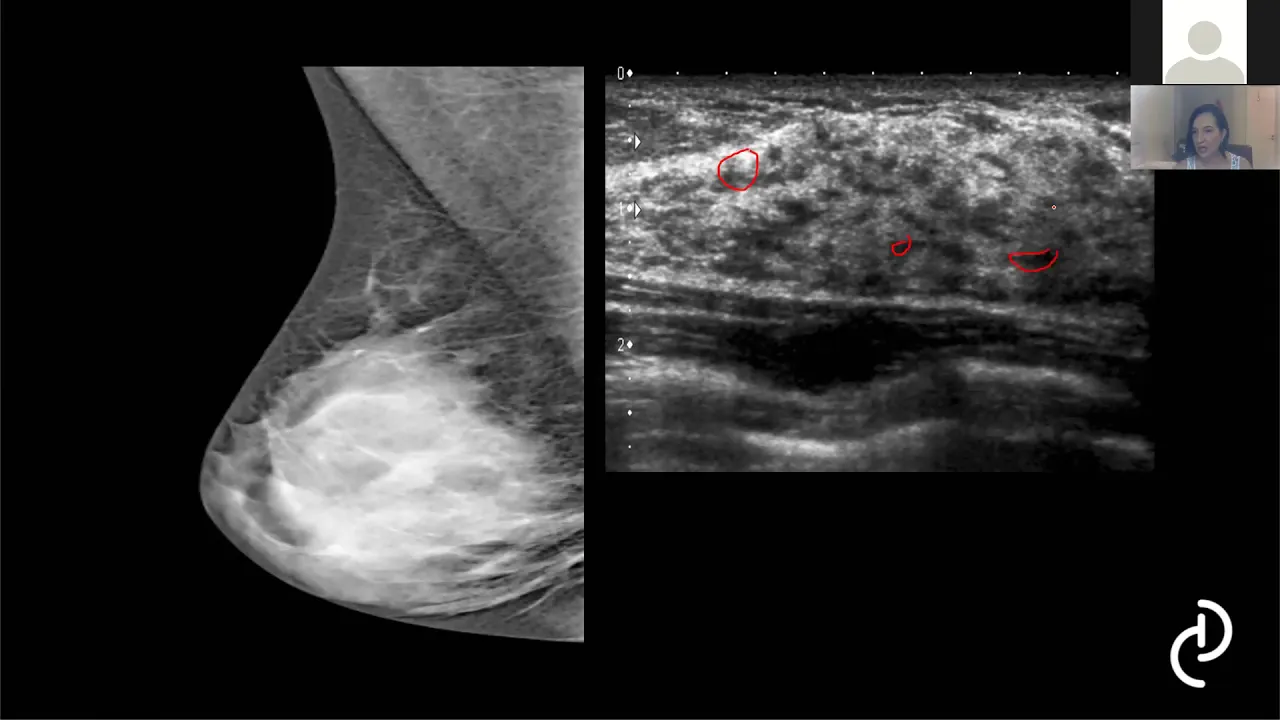

Aula Dra Daniella Prudente: Aprendendo interpretar o BIRADS com casos clínicos.